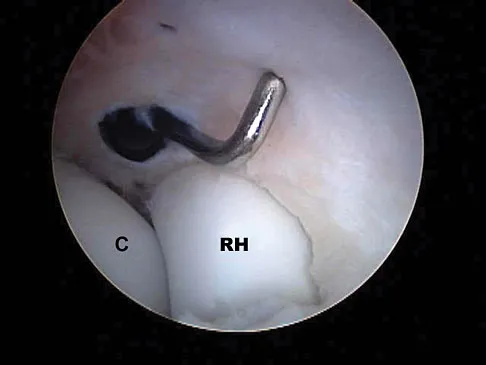

What neurovascular structure is in closest proximity to the probe in the arthroscopic view of the elbow shown in Figure 50?